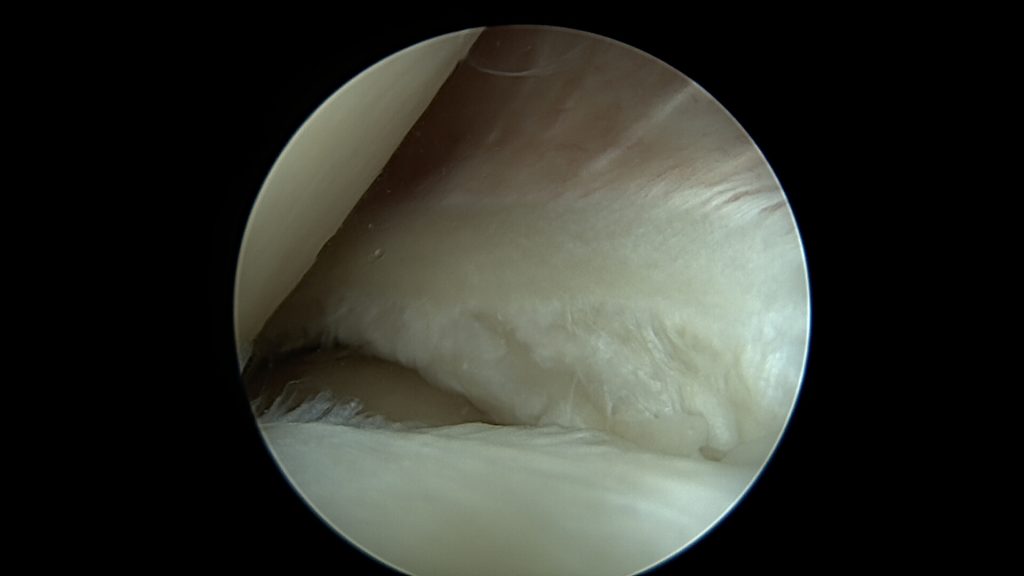

W tym przypadku jej proste przyszycie nie będzie możliwe, nie będzie po prostu stabilnych fragmentów łąkotki które można złapać szwem. Konieczne jest zastosowanie techniki „biokanapki”. Zabieg polega na owinięciu błoną kolagenową uszkodzonego fragmentu łąkotki, błona pełni tu rolę worka trzymającego włókna łąkotki razem. Szwy zakłada się poprzez błonę kolagenową stabilizując tym samym luźne uszkodzone fragmenty łąkotki. Na koniec zabiegu podaje się komórki macierzyste do środka stworzonej w ten sposób przestrzeni. Postępowanie pozabiegowe jest w tym przypadku określone odpowiednim protokołem rehabilitacyjnym.